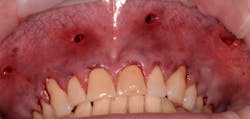

4. The surgical procedure is performed using a small gum-piercing instrument to create holes comparable with a laparoscopic procedure in medical surgeries. Four holes are usually enough to treat the entire arch (figures 11–12).

This new biological approach involving blood derivatives A-PRF and I-PRF combined with precision minimally invasive surgery for root coverage demonstrates faster healing without the need of a donor site. The morbidity of GDT is decreased and patient case acceptance is higher compared with traditional grafts. Before-and-after pictures are shown below (figures 15–22).